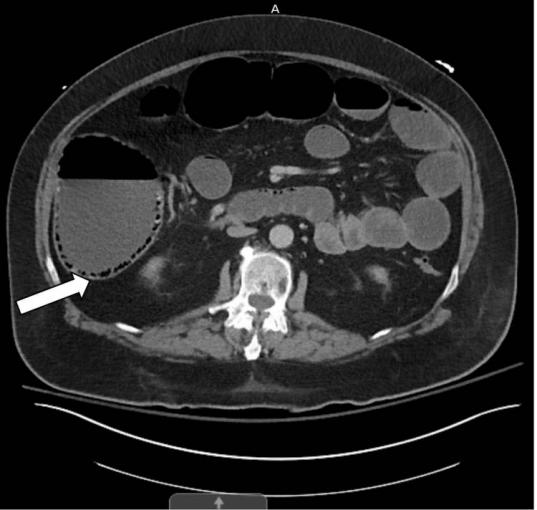

入院实验室数据如(表1)所示。腹部和骨盆的计算机断层扫描(CT)扫描和静脉注射(IV)造影显示结肠梗阻,膨胀的升结肠直径接近11cm,存在周围PI(图1)。横结肠也因积气而扩张,而降结肠扩张较少;在降结肠中部存在一个过渡点,没有观察到任何肿胀(图2)。

图1 腹部和骨盆的CT扫描显示,升结肠扩张,伴有肠周积气(箭头)